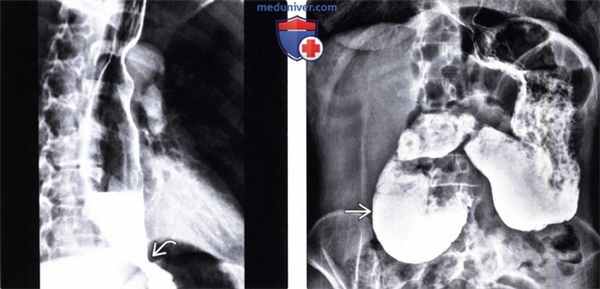

(Слева) На рентгенограмме пищевода, полученной при рентгеноскопии у женщины 38 лет со склеродермией, определяется стриктура в области пищеводно-желудочного перехода в сочетании с дилатацией пищевода и отсутствием перистальтики. Уровень жидкости и газа в просвете пищевода указывает на наличие стаза.

(Справа) На рентгенограмме этой же пациентки, у которой также имеется поражение кишечника, обусловленное склеродермией, выполненной во время рентгеноскопии желудка и двенадцатиперстной кишки, определяется выраженное расширение и отсутствие перистальтики двенадцатиперстной кишки и пилорического отдела.

о Поражение пищевода при склеродермии:

- Зияние кардиального сфинктера и гастроэзофагеальный рефлюкс приводят к развитию веретенообразной дистальной пептической стрикутры и (в некоторых случаях) грыжи пищеводного отверстия диафрагмы

- Отсутствие перистальтики в нижних 2/3 пищевода

- Поздние изменения: дилятация проксимальных отделов пищевода различной степени (от средней до значительной)

о Редко возможно формирование мешковидных выбуханий пищевода с широким основанием:

- У 70% пациентов со склеродермией имеется гастроэзофагеальный рефлюкс, из них у 37% развивается пищевод Барретта